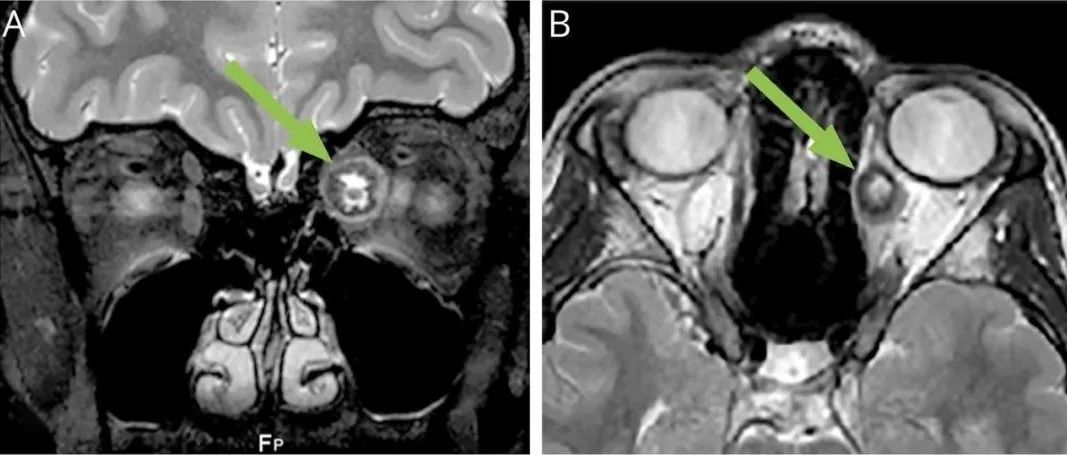

*仅供医学专业人士阅读参考视力下降原来还与这几种疾病有关01甲状腺相关眼病甲状腺相关眼病(TAO)是成年人最常见的眼眶病之一,属于自身免疫性疾病。为区别单纯有眼征与同时伴有甲状腺功能亢进者,习惯上将具有眼部症状同时伴甲状腺功能亢进者称为Graves眼病,而无甲状腺功能亢进及其病史者称眼型Graves病。TAO的三大特点是:眼睑退缩、眼球突出和眼外肌肥大。因每个TAO患者在发病过程中的时间和程度不同,即病变处于活动期或非活动期,眼组织受累的严重程度和部位不一样,故每个患者所出现的症状和体征不完全相同:一些病人有严重的眼球突出而没有眶周肿胀和眼外肌功能异常;另有一些病人有很轻微的眼球突出,但可能有明显的眶周软组织肿胀,畏光、流泪、眼胀痛等,甚至有一些病人开始就有复视而没有明显的眼球突出或眶周痛。...